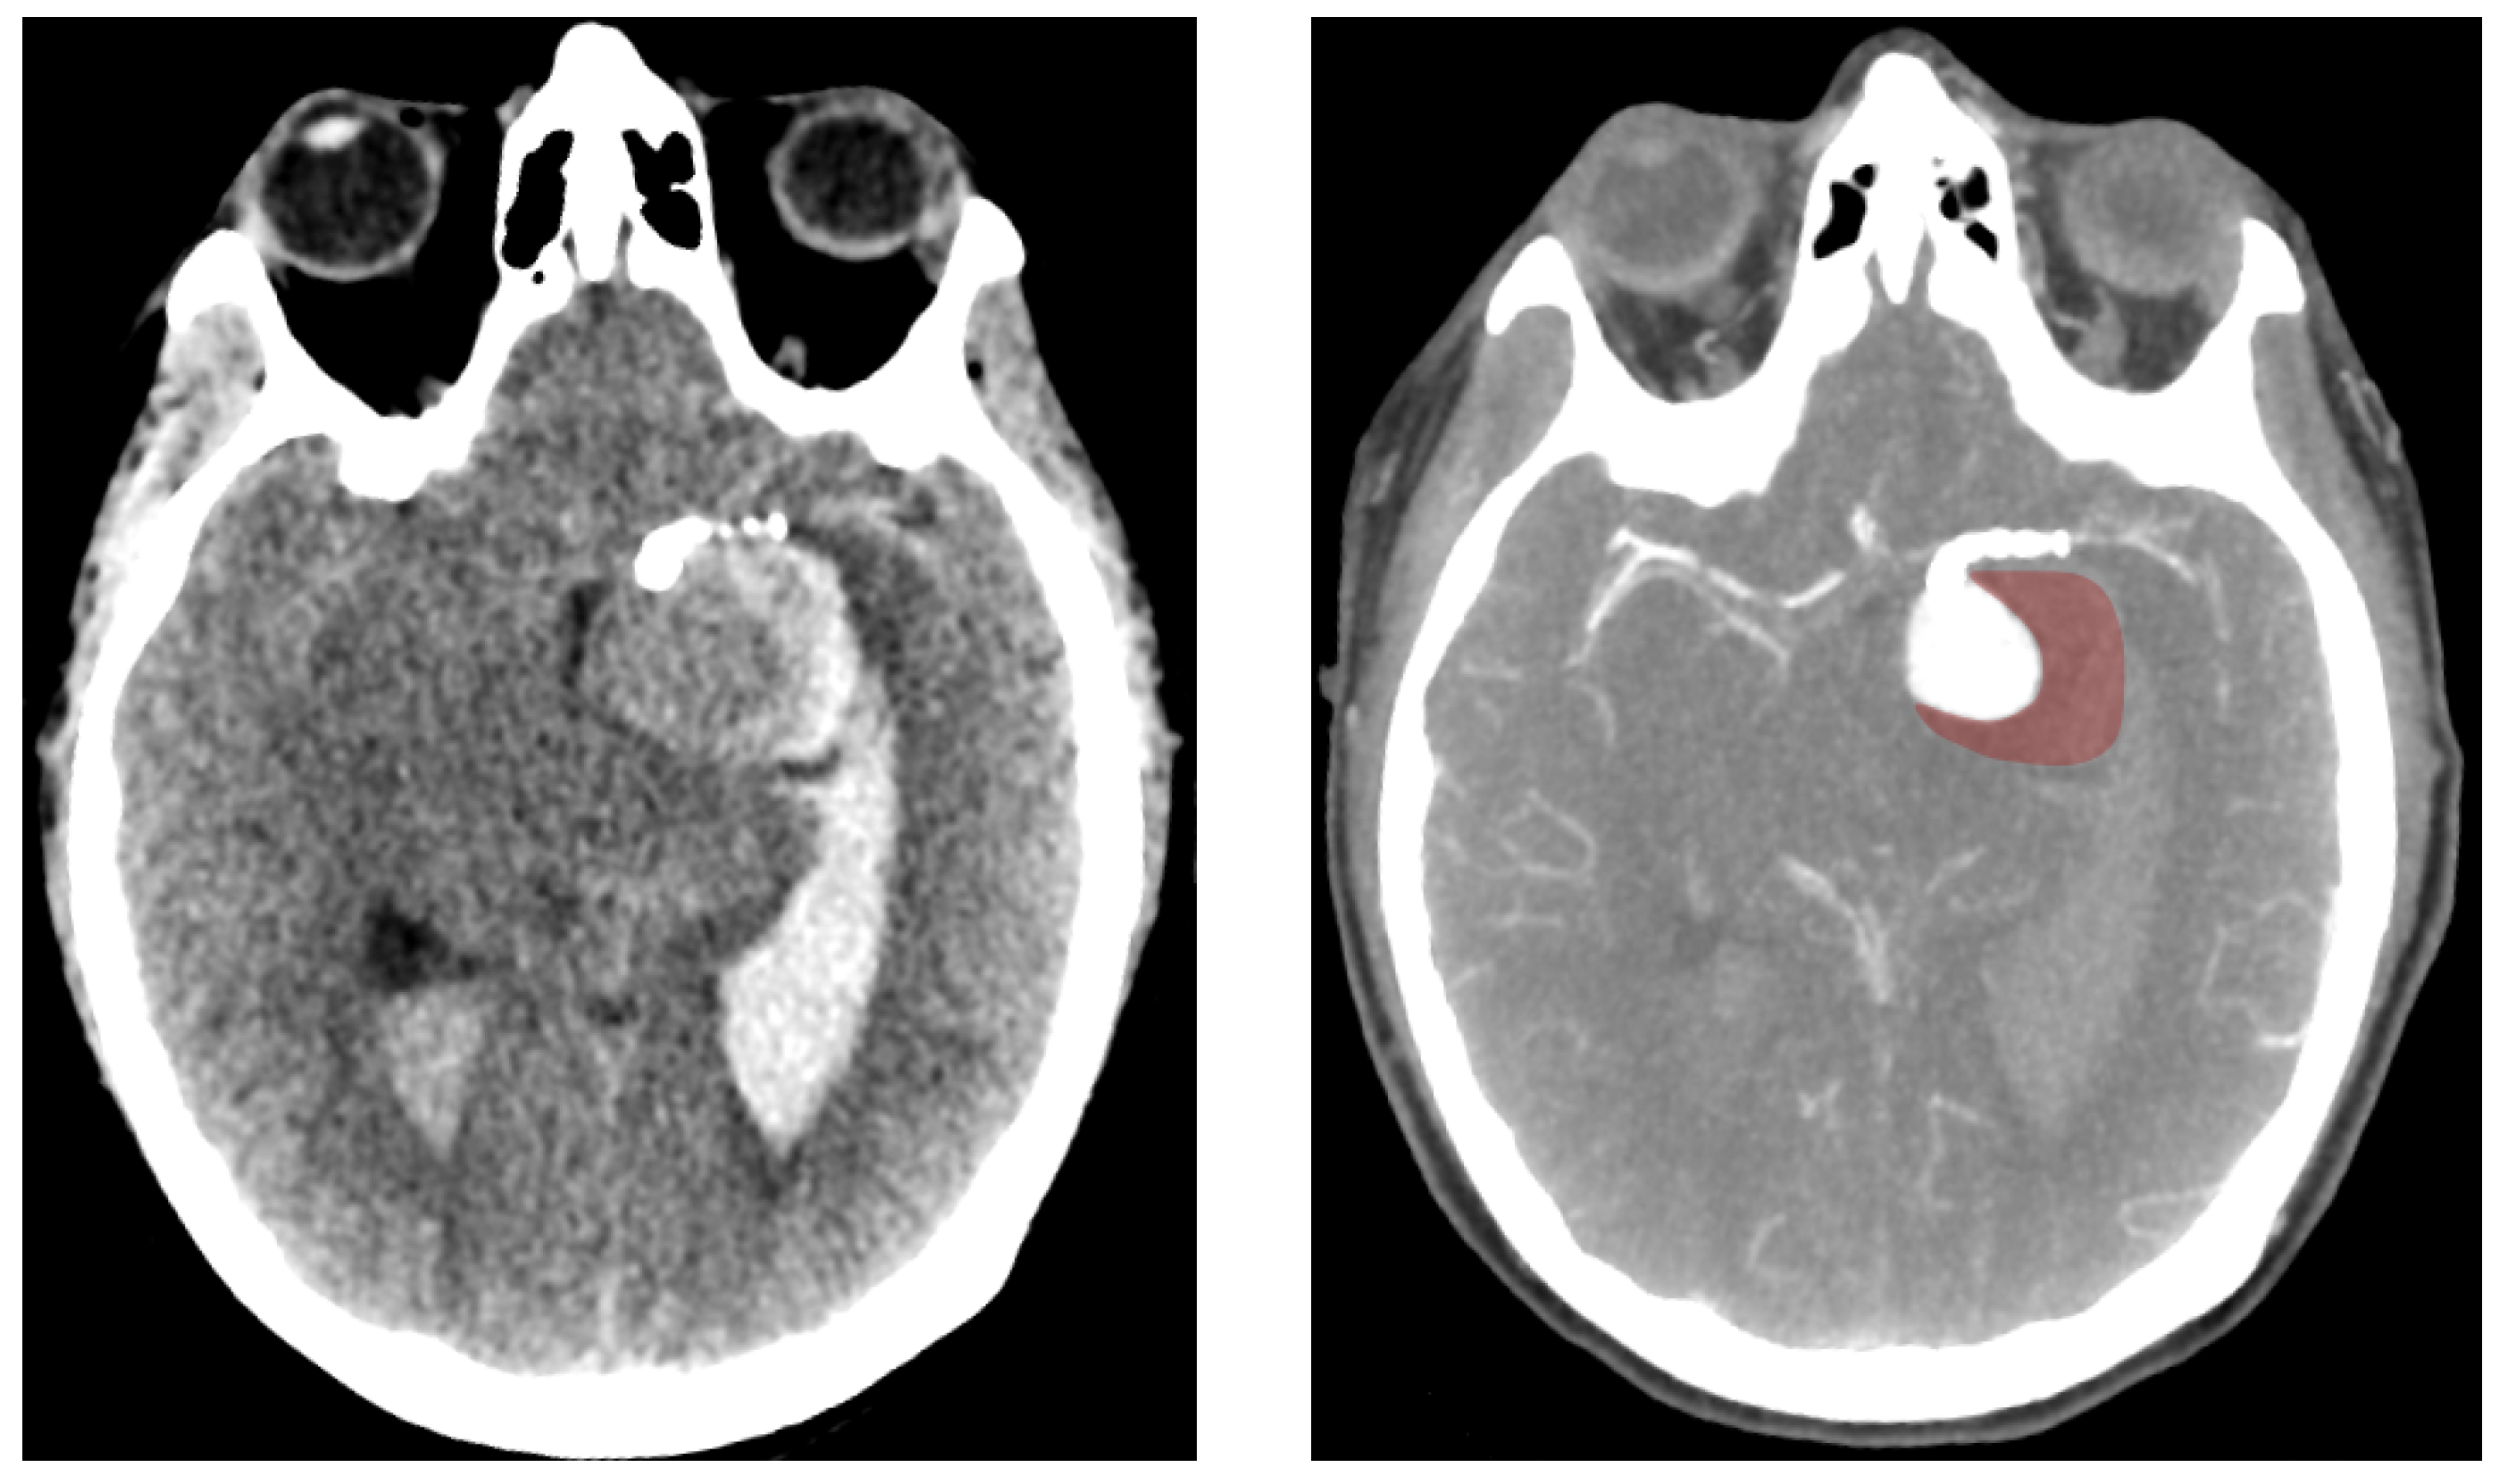

2.1. Patient Record